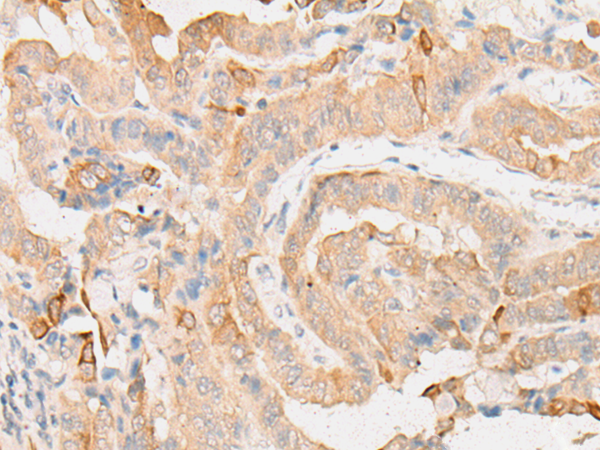

EIF2D |

eukaryotic translation initiation factor 2D |

IHC positive control: |

Human thyroid cancer and Human ovarian cancer |

IHC Recommend dilution: |

25-100 |